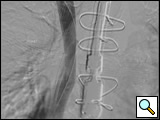

Figure 3: AP completion venogram on day 2 after mechanical thrombolysis and TPA infusion overnight and post-deployment of overlapping "kissing" Wallstents. Notice improved drainage into the right atrium on post-deployment venogram.

Re-imaging the following day or twelve hours later is necessary with the objective being bilateral upper extremity venograms showing a significant improvement in venous thrombosis and clot burden. Placement of two self-expanding Wallstents (Boston Scientific Inc., Natick, MA) stents centrally utilizing a "kissing stent" deployment technique [16] is warranted to avoid compression of the contralateral vessel and prevent compression of the flow channel: a 20 mm x 40 mm stent in the superior vena cava and right subclavian vein and a 14 mm x 40 mm stent in the innominate vein and superior vena cava (Figure 3). Stent sizes are selected according to patients' needs.